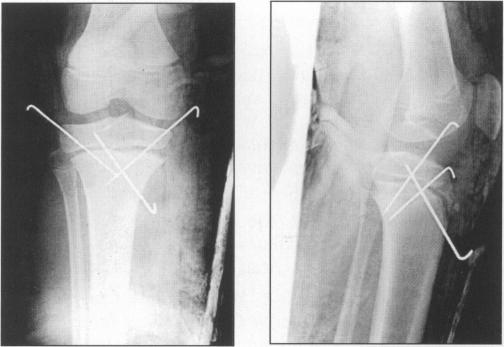

Salter harris type I fracture of the proximal tibial epiphysis.